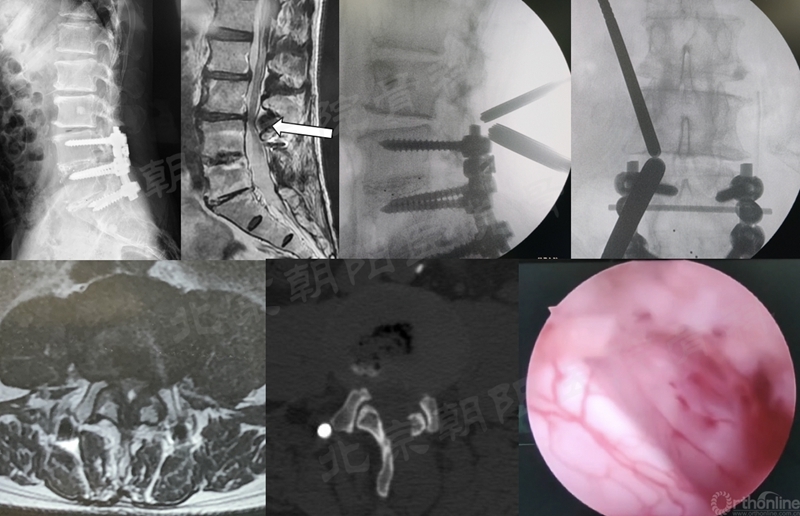

在经历15例UBE减压手术的学习曲线后,本团队进行了UBE腰椎减压融合术:#16例UBE,L4/5 LSS。

UBE-LIF手术步骤大致按常规开放手术:

1、显露L4椎板下缘-L4/5关节突-L5椎板上缘;

2、Kerrison钳减压L4下关节突(全部去除)-L5椎板上缘-L5上关节内侧缘(尽量靠外)-黄韧带整体切除;

3、硬膜外止血,显露椎间盘,确定椎间隙位置和方向;

4、椎间隙处理:骨刀,髓核钳,终板刮刀,Kerrison钳,电凝,+耐心;

5、自体骨+同种异体骨植骨;

6、可撑开融合器植入(透视定位);

7、检查遗漏的骨块,彻底清除神经周围的致压物;

8、必要时做对侧黄韧带减压;

9、经皮植入椎弓根螺钉,加压固定。

术前MRI和术中定位

椎间隙处理

植入可撑开Cage

术后X线片与CT(矢状面)

术前、术后MRI及CT(轴位)